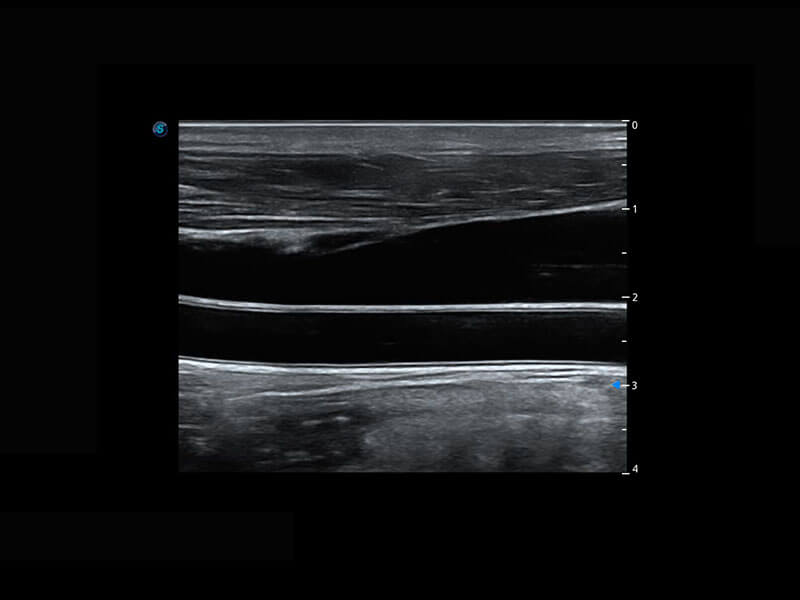

P60为盆底超声检查提供应用方案,多种腔内及腹部容积探头提供从二维、三维到四维的优异图像品质,实时快速三维容积数据获取,专业的测量工具包等人性化设计,为超声医生诊断提供有力保障。

能够简化盆底检查的操作流程,可在二维模式及三维成像模式下实现一键自动提取出标准切面、自动识别当前切面、自动测量,提升盆底检查的高效性,同时也能让青年医生快捷的获得准确的检查结果。